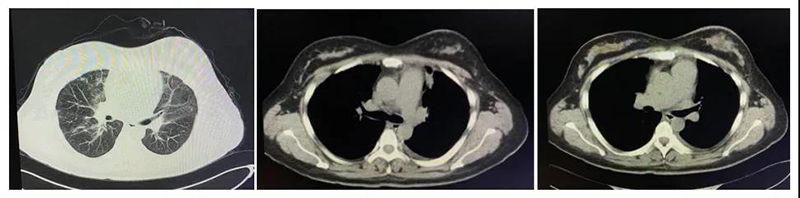

2周后,患者行第2周期化疗联合靶向治疗,并行肺CT检查评估病情,提示左乳肿物较前明显缩小(6.5cm×3.4cm→3.7cm×2.8cm),肺占位也明显缩小,间质性肺水肿明显好转,且胸水也得到有效控制,患者一般状态也较第一次入院明显改善,可平躺一段时间,且不需吸氧,可轻微活动,没有胸闷、气短等不适。目前,患者已顺利完成第3次治疗,已经可以平躺入睡,可从事轻体力活动,一般状态明显好转,生活质量明显提高,科室医护人员也为患者病情得到明显改善而欣慰。

第二次入院肺CT平扫